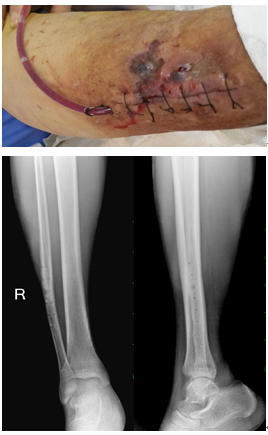

患者安徽天长居民,于2018年5月不慎外伤致右小腿疼痛、肿胀、活动受限,就诊当地医院,诊断为:右腓骨骨折,给予清创缝合、患肢制动、消肿等对症处理,后行手术治疗,术后切口反复渗液,在家自行换药处理后停止渗液,患者为进一步治疗来我院就诊。

患者入院后,完善相关检验检查,明确诊断,于2019年01月08日行手术治疗,1小时40分钟的手术顺利完成,术后予以抗感染、引流、石膏托抬高制动等对症处理。经术后对症治疗后,患者伤口愈合良好出院。

术前: